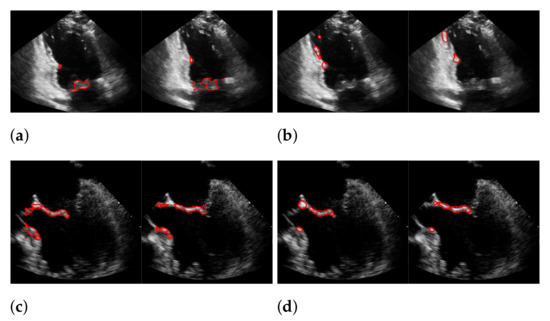

| Recall | Precision | f1-Score | |

|---|---|---|---|

| (a) | 0.494 | 0.692 | 0.565 |

| (b) | 0.44 | 0.558 | 0.45 |

| (c) | 0.165 | 0.551 | 0.244 |

| (d) | 0.378 | 0.43 | 0.377 |